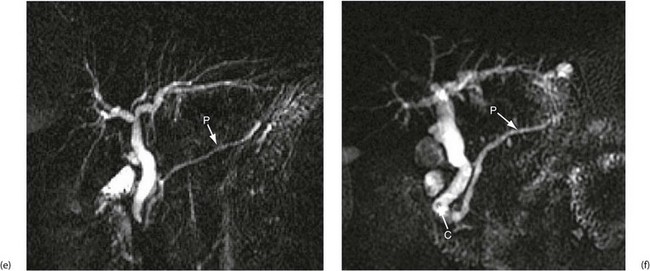

Magnetic resonance cholangio-pancreatography (MRCP) (Fig. 5.6 e and f): MRCP now produces images that rival the quality of ERCP. MRI differentiates tissues and organs by their varying water content. Bile and pancreatic juice are mostly water, hence MRCP gives clear images of bile in the gall bladder and ducts and outlines the pancreatic duct. It reveals filling defects caused by stones or tumours. MRCP can identify bile leaks, gallstones in the bile ducts, and duct obstruction from any cause. There are no known hazards. MRCP is increasingly used prior to ERCP for pancreatico-biliary investigation to reduce the number of patients requiring the more invasive investigation.

(e) and (f) Magnetic resonance cholangio-pancreatography (MRCP)

The technique produces images of static fluid, thus the images are of native biliary and pancreatic secretions. Each image was obtained in one second using a thick slab ‘projection’ method that generates images very similar to ERCP. The pancreatic duct in each image is labelled P. (e) An example of normal biliary and pancreatic duct systems. (f) A small calculus, C, in the distal common bile duct. There is also mild dilatation of the pancreatic duct with some side branches visible